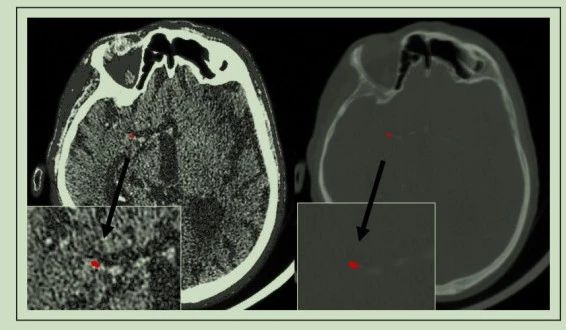

图1. 血栓在非增强CT和CTA上扫描密度的差异

急性缺血性脑卒中入院影像学评估必不可少,CT和CTA除了可直接明确闭塞血管部位,还会影响患者再通效果以及临床预后的诸多血栓特征,包括栓子长度、密度以及通透性等,进行评估的功能。血栓主要由纤维蛋白、血小板、红细胞以及部分白细胞组成,而通常认为卒中病因分型和栓子组织成分相关,在影像学上表现差异明显,大脑中动脉高密度征已经被证实和栓子中红细胞含量较高有关。血栓通透性的测量可由非增强CT和CTA成像根据造影剂的渗透程度来进行量化,而血管内治疗作为大血管急性闭塞的首选治疗方式,使得闭塞部位栓子得以取出体外进行研究。近期一项研究在基于CT和CTA下对血栓通透性进行分析,并分析其和血栓组成成分以及卒中类型的相关性。

所有的患者均经过非增强CT和薄层CTA进行扫描,血栓通透性使用非增强CT和CTA上HU值衰减差异进行表示(∆t)。通过对病理组织进行切片染色,对组织成分进行计数分析判断组织成分,本研究中所使用的病因分型方法为TOAST分型。首要终点事件为血栓通透性与血栓组成成分的相关性,次要观察指标为血栓病理组成成分和卒中病因的相关性。